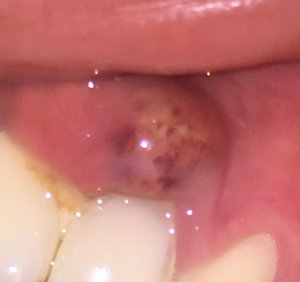

Два года назад мне выдрали зуб, было все хорошо два года. Запломбировали зуб поставили штифт, после возникла какая-то шишка. Пошла к хирургу, сказали киста, вырезали дней шесть назад, шишка стала еще больше, когда трогаешь чувствуешь, что она там есть, сегодня сходила к хирургу, сказала эту шишку постоянно массировать, и антибиотики прописали. Как говорит хирург, там опять образовалась пустота в этом же месте и по какой-то причине она не зарастает. Если она не пройдет, сказали пошлют на биопсию.

Мможет ли, что вот этот зуб со штифтом дает такую реакцию? Температура 37 - 37.3, у хирурга дошло уже дело до биопсии. Подскажите, может, и не надо эту шишку трогать, это же воспалительный процесс какой-то?

Возможно имеется припухлость, и это неотъемлемая часть обострения. Да, имеется костный дефект и зуб, который требует лечения ввиду неграмотного эндодонтического лечения, повлекшего за собой периодонтит. Я вам уже писал, об этом. На мой взгляд, ваш доктор немного лукавит, и биопсия тут вообще не нужна. Даже немного смешно читать такие рекомендации врачей. Сделайте К/Т (трехмерный снимок) и обратитесь к грамотному врачу.